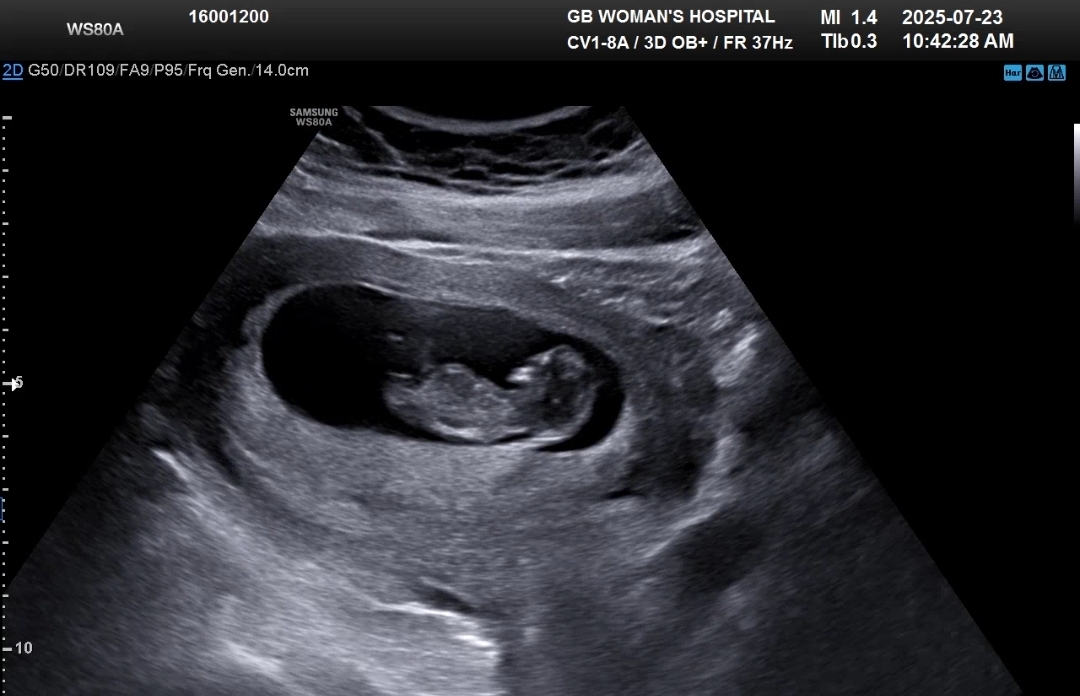

중간에 딱 1번 살짝 분홍빛 피가 비쳐서 걱정이 되었는데 아기도 잘 크고 있고 (드디어 약간의 인간비스무리한 형태가 보임ㅋㅋ)

자궁에 피고임도 전혀없고 다만 경부가 살짝 부어있어서 경부에 있던 피가 살짝 나온거 같다고 하셨다

확실히 조금 더 꼼꼼하게 봐주는 느낌이 있었다